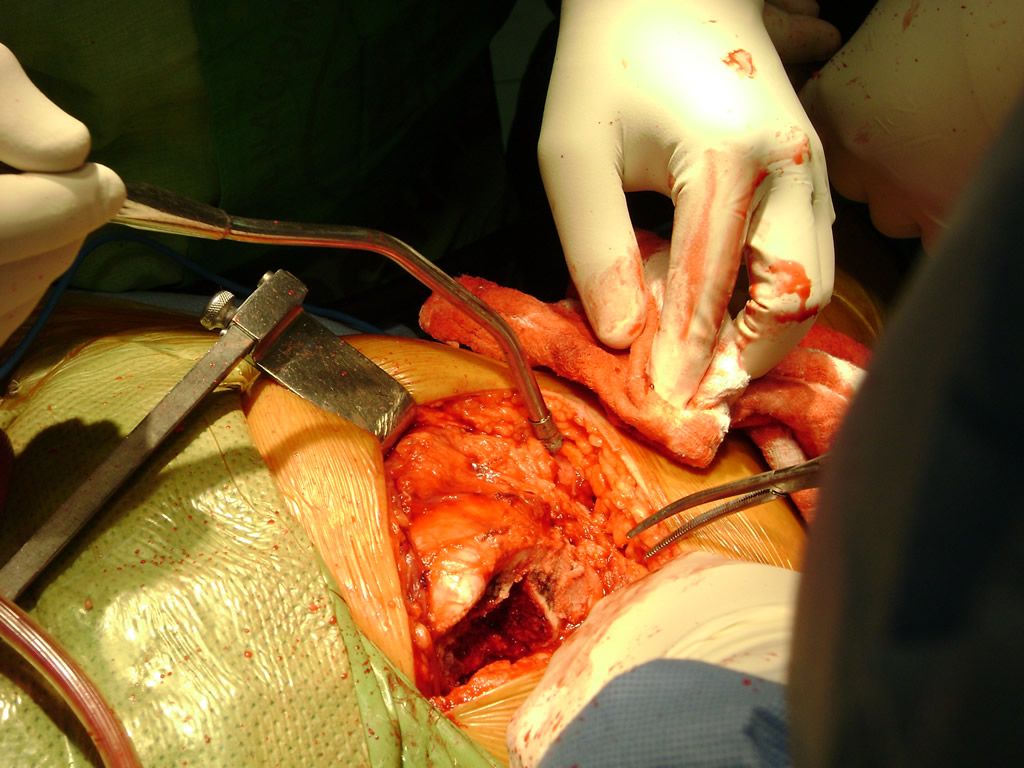

Cirugías de Hombros - Perone y Tibia

Debido a la fina cobertura de piel que recubre la tibia y el peroné, las fracturas generalmente son abiertas, es decir, el hueso roto rasga la piel, atravesándola. Las fracturas de tibia y peroné generalmente se producen por un fuerte impacto o torsión.